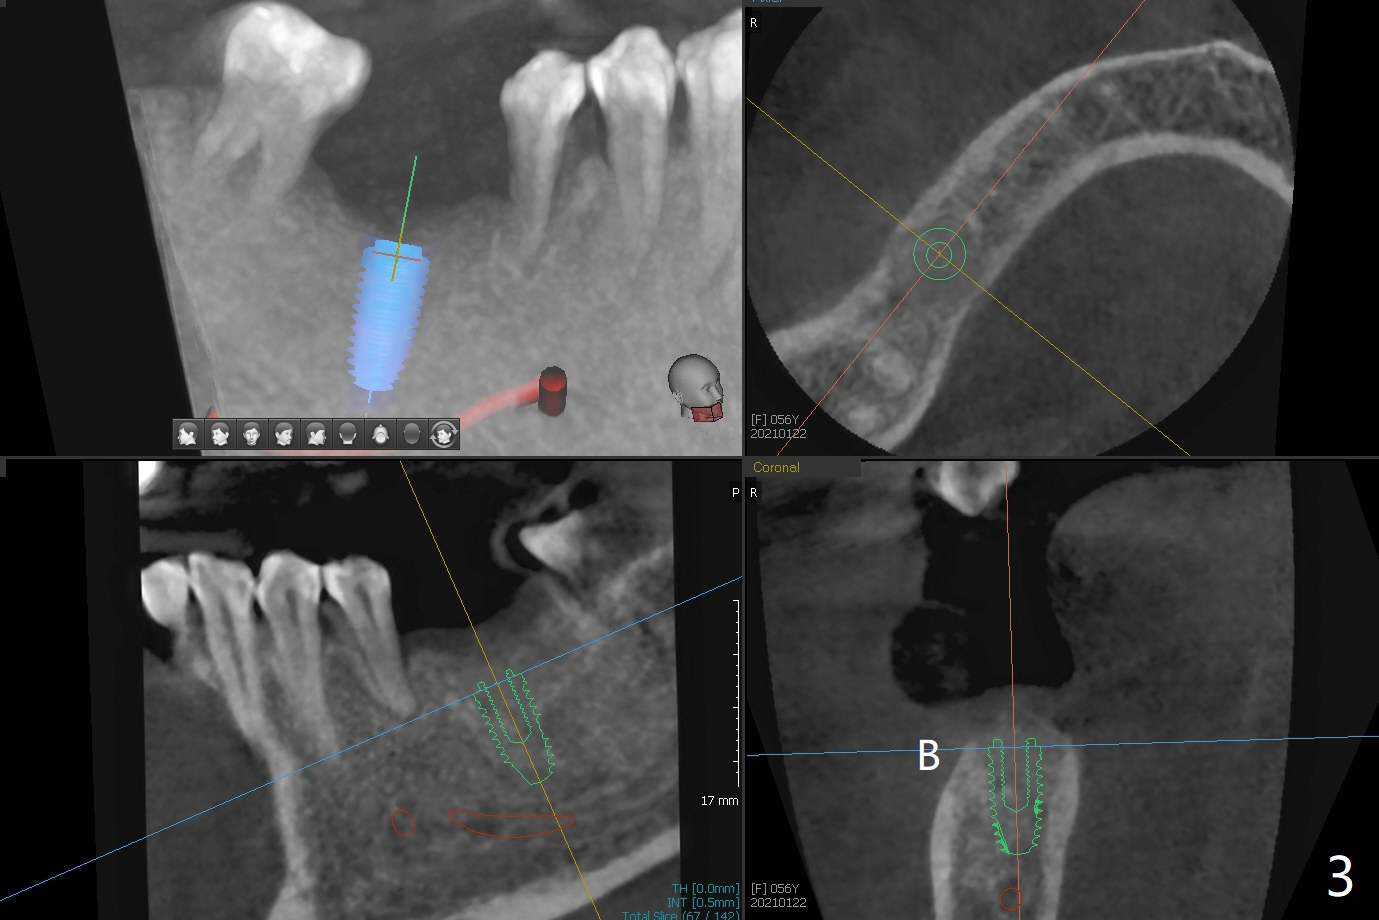

即刻植牙对害怕病人有一个好处,快速结束治疗,安慰病人可是一个麻烦事。即刻种植也可以发生于拔除失败植体之后。今天拔除的失败植牙不知厂家,基台螺丝刀对不上号,所以当植体取出时,病人和我都筋疲力尽,临时决定不做即刻种植。但是出现一个问题,事先准备粘性骨块不够,形成粘性骨块后的上清液不再形成粘性骨块,虽然仍然含有血小板,这样松散的骨粉如果放在牙槽窝上端比较容易丢失。我们解决方法是先把不粘稠的骨粉放在底层(图一:N),把粘性骨块放在上面(S),之后放置PRF膜以及不可吸收膜,使用PTFE缝线和牙周敷料。术后疼痛严重,创伤大。术后4个月牙槽嵴中央塌陷(图二)。不过还能植入5x10毫米植体(图三,四)。Return to Armaments No Deviation Xin Wei, DDS, PhD, MS 1st edition 09/15/2020, last revision 04/06/2021